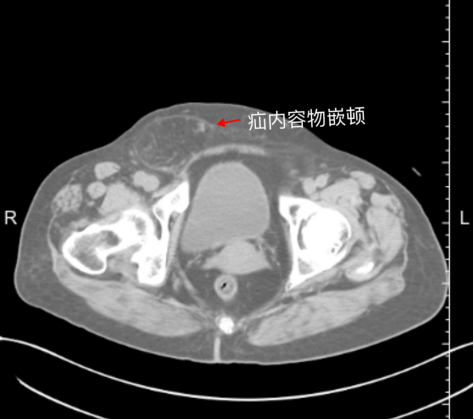

二是有导致腹压增大的原因,比如前列腺增生、长期便秘、慢性咳嗽等等,平时一般不会有太多不适感,如果发病时间长了则有局部或者下腹部坠痛感,严重者一旦发生嵌顿,会有剧烈疼痛。

小疝好补,老疝不仅手术难度大,术后并发症也多,也更容易复发,而一旦发生嵌顿,必须做急诊手术,甚至有肠坏死的风险,那就得不偿失了。